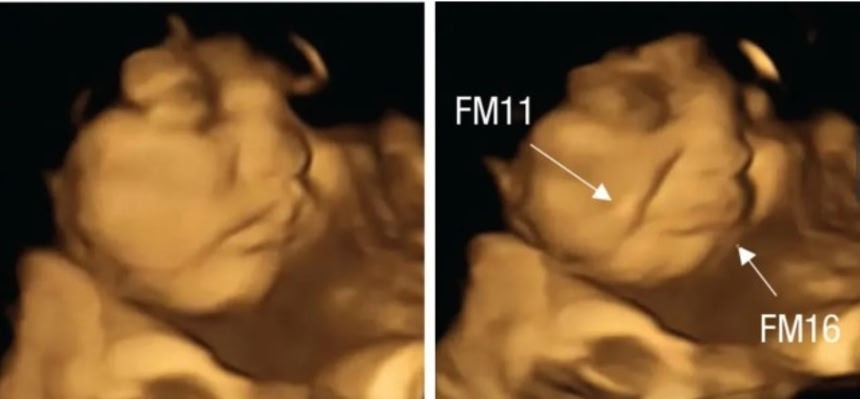

赤ちゃんはお腹にいるときから味覚や嗅覚に反応していた。ニンジンは笑顔、ケールはしぶい顔